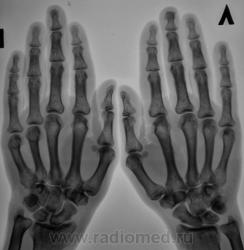

Пол пациента: Женский пол Тип патологии: Другое Область исследования: Скелетно-мышечная система Методы исследования: Rg Пациент с диагнозом "ревматоидный артрит" направлен на рентгенографию кистей. https://radiomed.ru/sites/default/files/styles/case_slider_image/public/user/12/2.pb100037a.jpg?itok=yFjpd1IX https://radiomed.ru/sites/default/files/styles/case_slider_image/public/user/12/3.pb100038.jpg?itok=92itQ56R https://radiomed.ru/sites/default/files/styles/case_slider_image/public/user/12/4.pb100038a.jpg?itok=rsA7mSo8 ID:8677 Чт, 11/11/2010 - 01:03 #1 Makcimalist Не на сайте Был на сайте: 11 лет 8 месяцев назад Зарегистрирован: 08.05.2010 - 14:28 Публикации: 1994 - специфич. признаков начальных стадий РА не нашёл... -------------- "Просто, по видимости, не видеть логики в очевидных вещах - это тоже одно из свойств некоторых умов, наряду с грустными думами о свойствах ума других." © Vega 08/10/2011 Чт, 11/11/2010 - 14:44 #2 Катенёв Валенти... Не на сайте Был на сайте: 7 лет 2 недели назад Зарегистрирован: 22.03.2008 - 22:15 Публикации: 54876 Норму писать? Сб, 13/11/2010 - 01:28 #3 Makcimalist Не на сайте Был на сайте: 11 лет 8 месяцев назад Зарегистрирован: 08.05.2010 - 14:28 Публикации: 1994 Начальные проявления остеоартроза пястно-фаланговых,м/фаланговых суставов... (Норма бывает п/е рождения... и то не всегда...) -------------- "Просто, по видимости, не видеть логики в очевидных вещах - это тоже одно из свойств некоторых умов, наряду с грустными думами о свойствах ума других." © Vega 08/10/2011 Сб, 13/11/2010 - 19:53 #4 Глазков Игорь А... Не на сайте Был на сайте: 9 месяцев 2 недели назад Зарегистрирован: 19.12.2008 - 20:41 Публикации: 1597 Имеются кистовидные просветления костной ткани в эпифизах костей. Прийди к Себе

- специфич. признаков начальных стадий РА не нашёл...

Начальные проявления остеоартроза пястно-фаланговых,м/фаланговых суставов...

Имеются кистовидные просветления костной ткани в эпифизах костей.